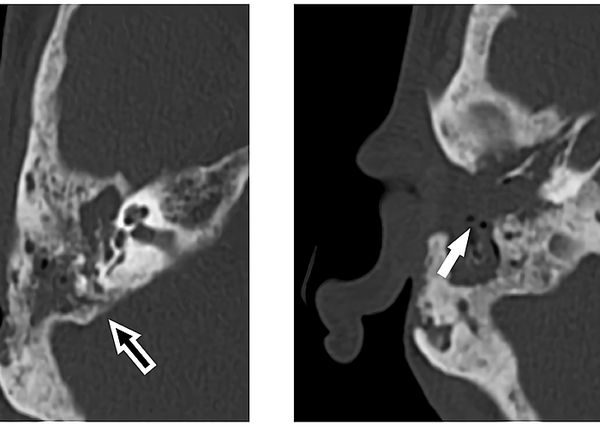

Seorang pasien berusia 65 tahun datang ke rumah sakit dengan masalah telinga. Setelah diperiksa, ternyata ada banyak belatung di telinganya.